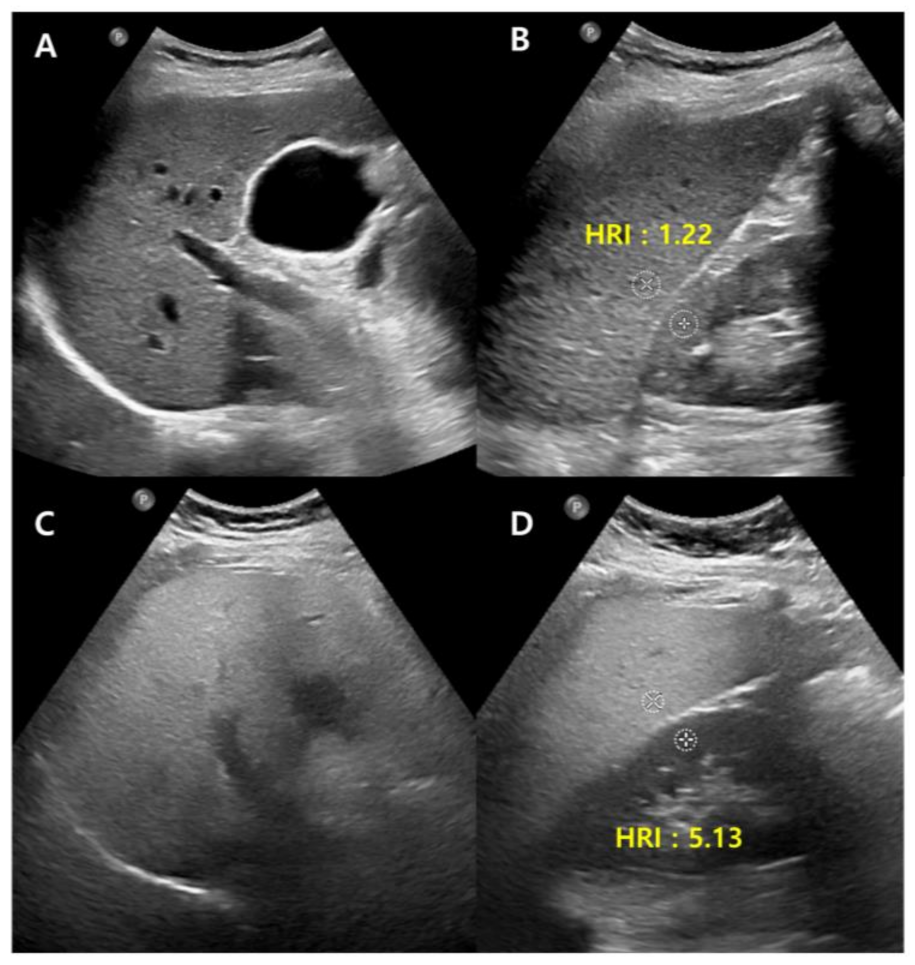

B-mode US allows an estimate of steatosis severity according to the subjective examination of sonographic patterns [20]. The severity is generally categorized as absent, mild, moderate, and severe. Mild hepatic steatosis is seen as a more diffuse increase in liver echogenicity than the renal cortex, moderate hepatic steatosis is seen as an increase in liver echogenicity with impaired visibility of the diaphragm and portal vein wall, and severe hepatic steatosis is seen as a large increase in liver echogenicity and poor visualization of the diaphragm, portal vein wall, and posterior regions of the right liver lobe (Figure 1).

Figure 1. Conventional US examination for evaluation of hepatic steatosis: normal (A), mild (B), moderate (C), and severe (D) hepatic steatosis. The vessel (arrow) and diaphragm (arrowhead) are well distinguishable in a normal liver (A). Liver parenchymal echogenicity is increased compared with renal cortical echogenicity in mild hepatic steatosis (B). In moderate hepatic steatosis (C), the vessel wall echo becomes obscured (arrow), and the diaphragm is partially visible (arrowhead). Due to a marked increase in liver echogenicity in severe hepatic steatosis (D), there is blurring and poor visualization of the diaphragm (arrowhead), as well as deep posterior parts of the right liver lobe.